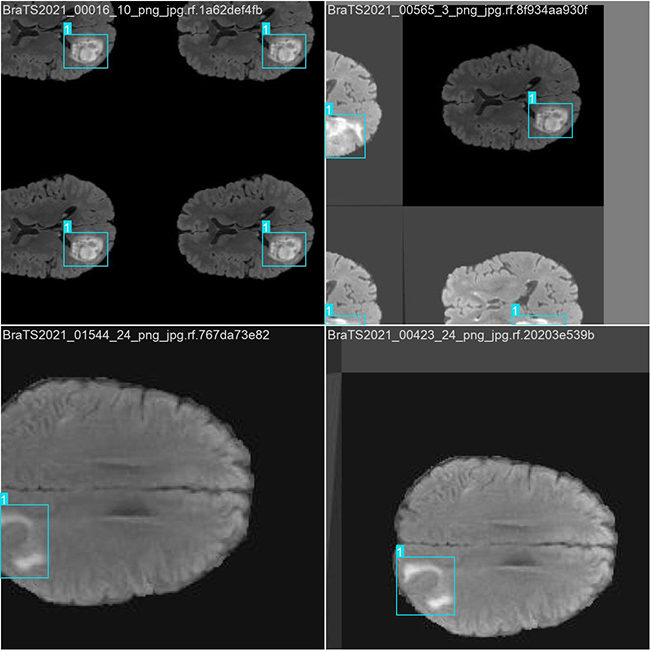

2.数据集准备与训练

本研究使用了包含脑肿瘤图像目标的数据集,并通过 Labelimg 标注工具对每张图像中的目标边界框(Bounding Box)及其类别进行标注。基于此数据集,采用 YOLOv8n 模型进行训练。训练完成后,对模型在验证集上的表现进行了全面的性能评估与对比分析。整个模型训练与评估流程包括以下步骤:数据集准备、模型训练、模型评估。本次标注的目标类别主要集中于脑肿瘤图像目标。数据集总计包含 3841 张图像,具体分布如下:

训练集:2688 张图像,用于模型学习和优化。

验证集:768 张图像,用于评估模型在未见过数据上的表现,防止过拟合。

测试集:385 张图像,用于最终评估模型的泛化能力。

部分数据集图像如下图所示:

部分标注如下图所示:

这种数据分布方式保证了数据在模型训练、验证和测试阶段的均衡性,为 YOLOv8n 模型的开发与性能评估奠定了坚实基础。